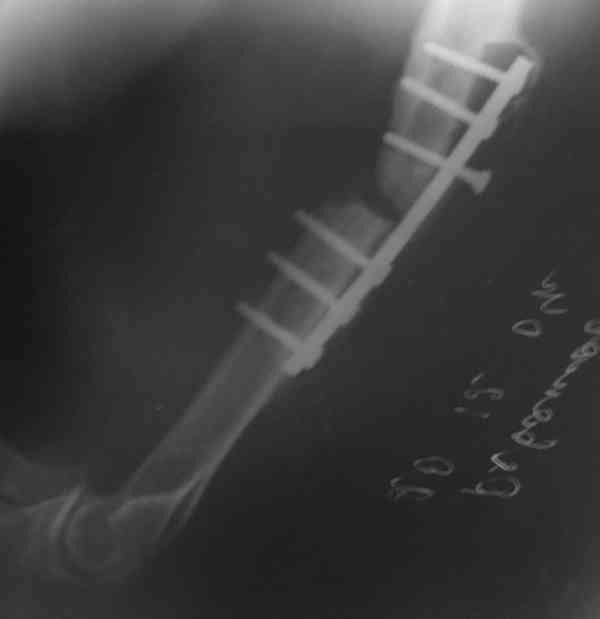

Штифт - отвисание проксимального отдела - накостный остеосинтез, нагноение, АФВ с ревизиями раны, опять пластина и снова нестабильность. Была удалена пластина и выполнен БИОС штифтом ChM (ДЕОСТ). Через 2 нед. пациент сел за руль и вышел на работу. Причем так и работает до сих пор уже 1,5 года, хотя полного сращения мы вроде бы не достигли ( снимки пришлю позже) - пациент не приходил на осмотры, общался только по телефону.

Второй пациент перенес два неудачных накостных остеосинтеза на фоне пареза лучевого нерва. Была удалена пластина и выполнен БИОС штифтом ChM (ДЕОСТ) - это была наша первая операция БИОС.